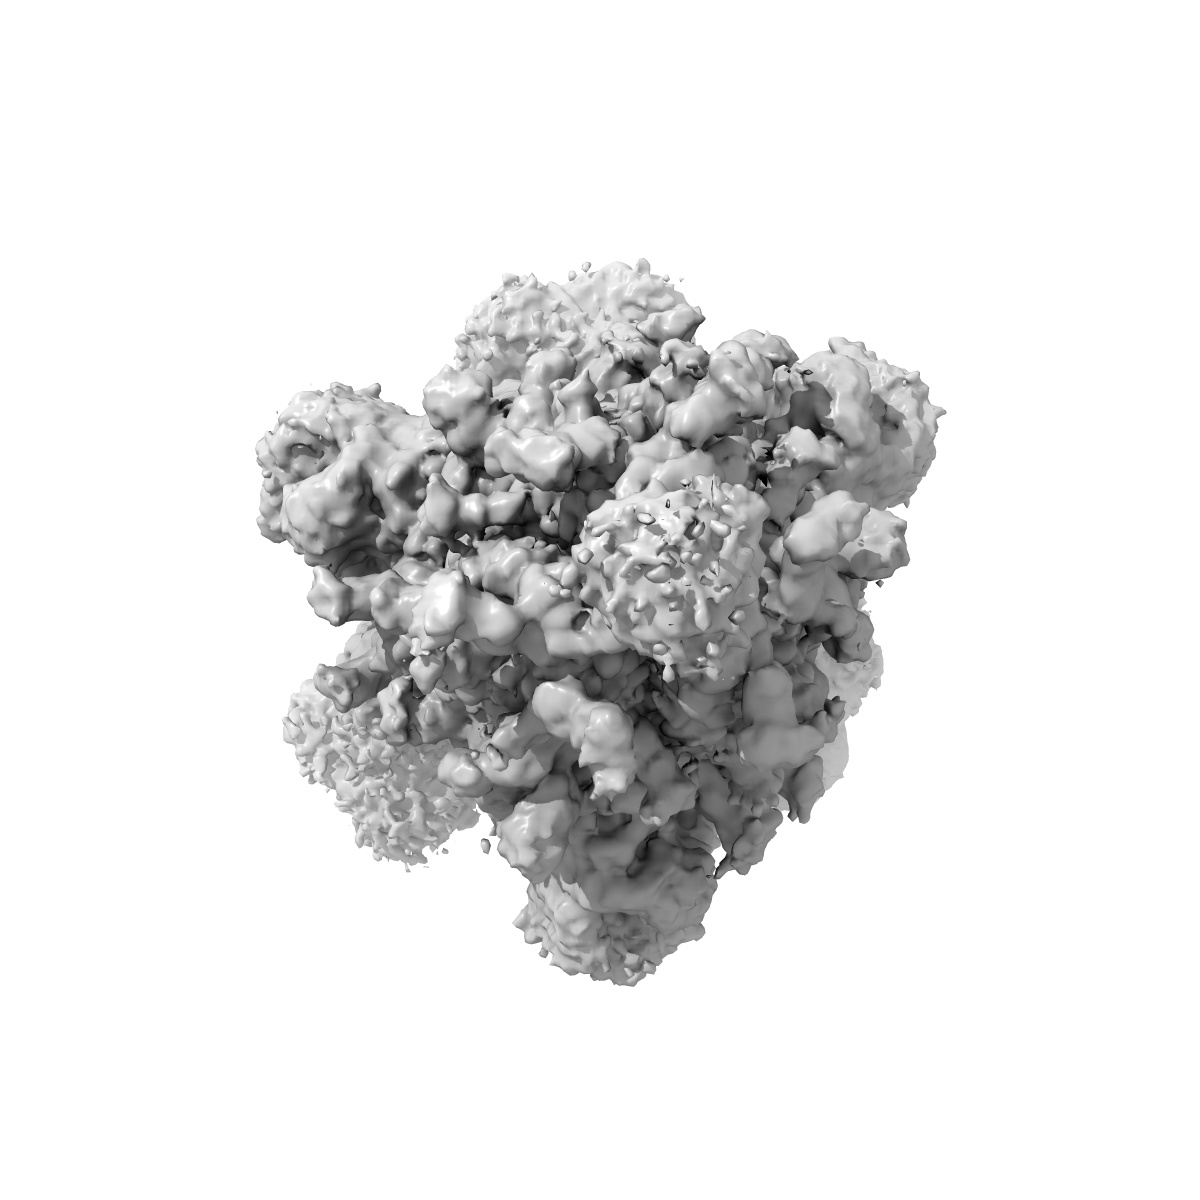

Cryo-EM structure of SARS-CoV-2 S-Gamma variant (P.1) in complex with Angiotensin-converting enzyme 2 (ACE2) ectodomain, three ACE2-bound form conformation 1

Sample Organism: Severe acute respiratory syndrome coronavirus 2, Homo sapiens

Sample: SARS-CoV-2 spike glycoprotein complex with Angiotensin-converting enzyme 2 (ACE2) ectodomain

Fitted models: 7v82

Yang TJ , Yu PY , Chang YC , Hsu STD